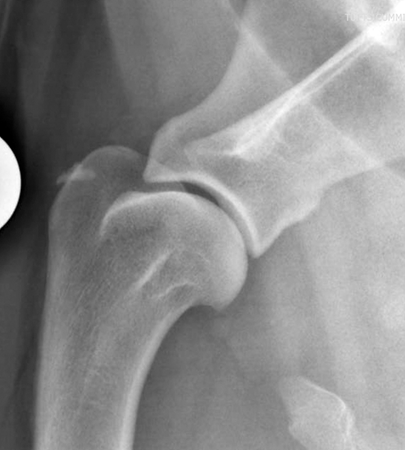

What should be seen in a well positioned lateral view radiograph of the shoulder?

In a well positioned radiograph the joint space should be well visualised and there should be no overlying tissue

Some radiographers deliberately try to overlie the shoulder joint with the trachea to increase contrast

label

acromion process

spine of scapula

scapula

humeral head

humerus

glenoid cavity

greater tubercle